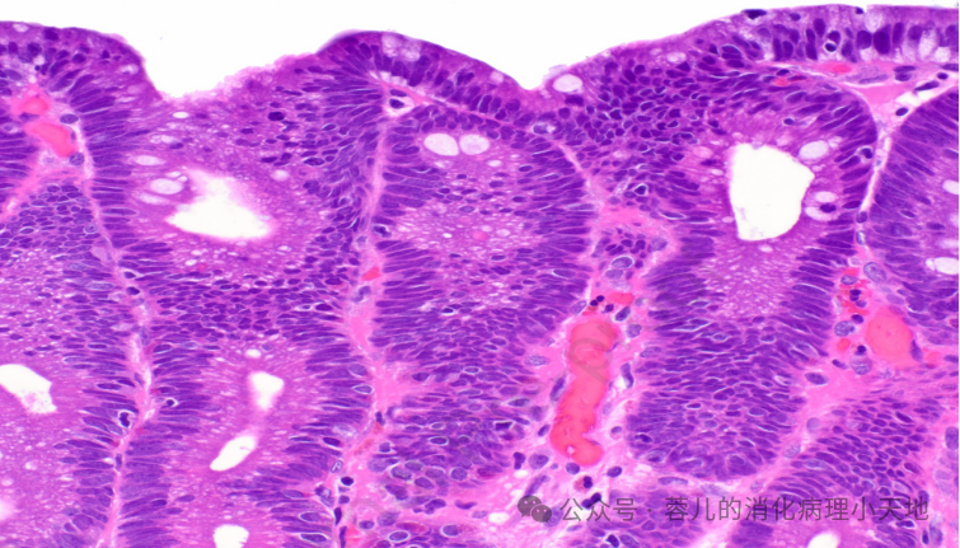

胃小凹发育不良,胞质嗜酸性,核增大、染色质增多,轮廓不规则

组织学特征:胞质嗜酸性,核增大、染色质增多,轮廓不规则

好发部位:胃体部胃泌酸黏膜表面